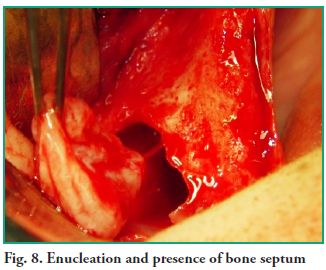

An ostectomy was performed using a rotary instrument and copious irrigation with normal saline is applied to enlarge the fenestration in order to improve visibility. The lesion was fully removed with sinus lift curettes using the enucleation and curettage technique, and the exeresis of the bone septum that divided the lesion was performed afterwards (Figs. 7, 8 and 9). Finally, closure was performed using continuous suture with 5-0 nylon thread (Fig. 10).

An ostectomy was performed using a rotary instrument and copious irrigation with normal saline is applied to enlarge the fenestration in order to improve visibility. The lesion was fully removed with sinus lift curettes using the enucleation and curettage technique, and the exeresis of the bone septum that divided the lesion was performed afterwards (Figs. 7, 8 and 9). Finally, closure was performed using continuous suture with 5-0 nylon thread (Fig. 10).